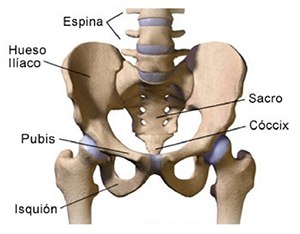

Cirugías de Calcaneo - Cadera

La cirugía de fractura de cadera se realiza para reparar una ruptura en la parte superior del hueso del muslo. Este hueso se denomina fémur.

La cirugía de fractura de cadera se realiza para reparar una ruptura en la parte superior del hueso del muslo. Este hueso se denomina fémur.

Es parte de la articulación coxofemoral. Si una fractura de cadera no recibe tratamiento, es posible que deba permanecer en una silla o en la cama.

Esto puede llevar a otros problemas de salud potencialmente mortales, sobre todo si usted es una persona mayor.

A menudo se recomienda la cirugía para reparar la fractura debido a dichos riesgos.